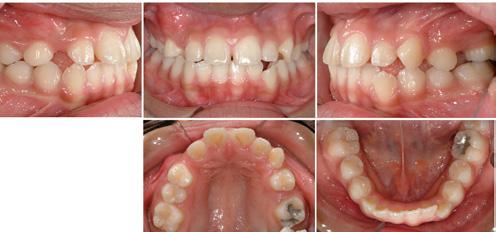

A healthy 13 1/2 year-old Asian girl was referred by her general dentist. Interestingly, this general dentist provides most of the orthodontic treatment for his patients, including comprehensive fixed appliance therapy. The patient presented without any primary teeth. However, the permanent maxillary second molars, right canine, and left second premolar were unerupted. It was obvious that there was a significant maxillary arch length insufficiency. All permanent mandibular teeth were present, along with mild crowding in this arch. The patient’s oral hygiene was excellent, as was her overall dental health. Orthodontic treatment was recommended, beginning with the collection of INITIAL records and treatment planning.

The INITIAL intraoral photographs (Figure 2) highlight the disparity in crowding between the maxillary and mandibular arches, as mentioned above. The right molar relationship is Class I; the left molar relationship is strong Class I. The left canine relationship is Class III. There is minimal depth of bite and no canine guidance in lateral excursions.

Figure 2: Initial intraoral photographs